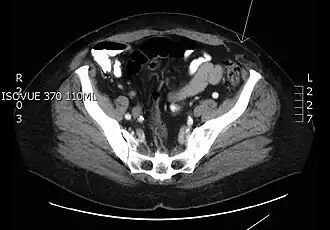

| CT Scan transverso de uma hérnia Spiegeliana. | |

- Hérnia de parede lateral ou de Spiegel: Resultado de um defeito da parede abdominal, o intestino atravessa a aponeurose spigeliana, entre a linha semilunar (transição do músculo para a aponeurose no músculo transverso abdominal) e a borda lateral do músculo reto abdominal. [3]

O diagnóstico é clínico. A herniação, em caso de dúvida, pode ser identificada com tomografia computadorizada ou ultrassonografia.[5]